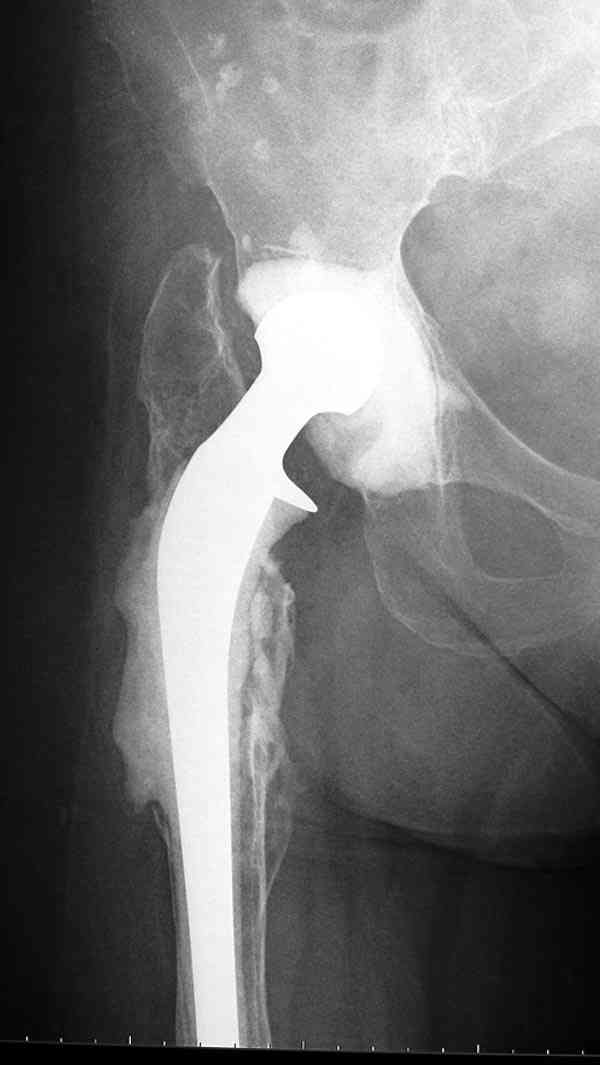

Недавно на сайте выставлял случай восьмилетнего наблюдения после инфицированного эндопротезирования, кроме ножки из цемента с антибиотиком также был сооружен и ацетабулярный компонент.